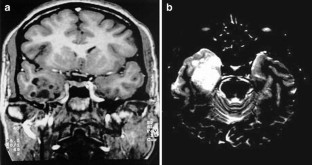

Magnetic resonance imaging combined with electroencephalography (EEG), electrocorticography, and depth-electrode EEG was valuable to localize complicated epileptogenic zones of the patients with DNT. Neuropathological examinations of the peritumoral cerebral cortex presenting abnormal spikes showed different histopathological grades of neuronal migration disorder (NMD). The tumor cells in DNT disclosed increased immunopositivities of N-methyl-d-aspartate receptor 1 (NR1) and NR2A/B, and peritumoral epileptogenic NMD revealed increased immunopositivities of GluR2 and GluR3. The amplification of ionotropic glutamate receptor subunits in the tumor and peritumoral NMD may be the underlying cause of epileptic seizures in DNT patients.

Fig. 2